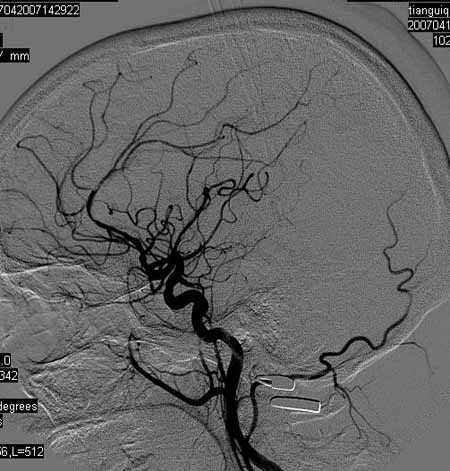

标题: DSA0093:脑血管造影

女,63岁,左侧额、枕叶脑梗塞。

右肾动脉及左颈内动脉起始部狭窄(考虑动脉硬化引起的),大脑中动脉分支减少.